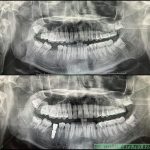

Sắp tới ngày thương binh liệt sĩ 27 tháng 7 tôi xin lên 1 video về chú Nhân, là 1 cựu chiến binh tham gia nhiều năm trong chiến tranh Việt Nam. Năm nay chú đã 74 tuổi và được cấy ghép 3 implant răng 35, 37 (hàm dưới bên trái) và răng 45 (hàm […]